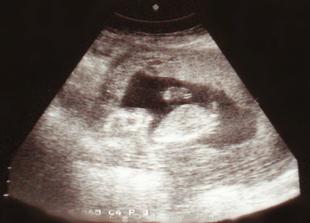

* "překontrola" 14. 8. a na ultrazvuku už bliká!!!! srdíčko (7 tt)